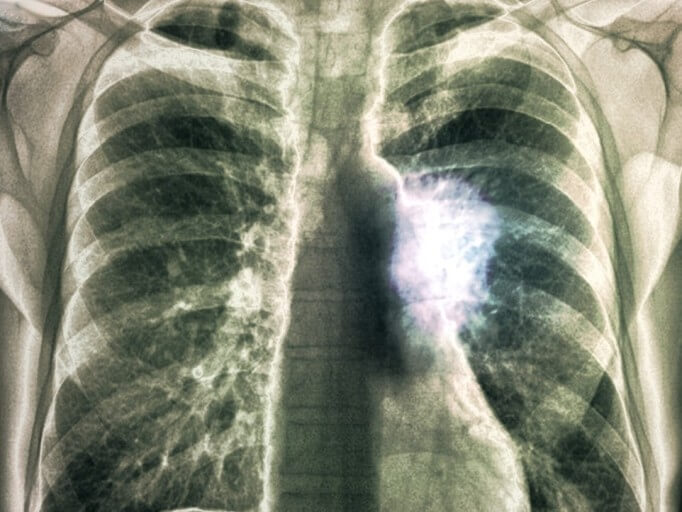

2차성 기흉은 교통사고나 외상 등의 충격으로 인해 폐가 손상될 경우 발생합니다.

만성 폐 질환이나 결핵, 암 등으로 인해 발생할 수도 있고, 유전적 요인으로 인하여 발생할 수도 있습니다.

3) 외상성 기흉

외부 충격에 의해 폐가 손상되면서 공기가 흉막 안으로 새어 나오는 것을 의미합니다.

교통사고나 상해로 인해 흉부 손실이 생길 경우 공기가 쌓일 수 있으며, 심할 경우 긴장성 기흉이 발생할 수도 있습니다.